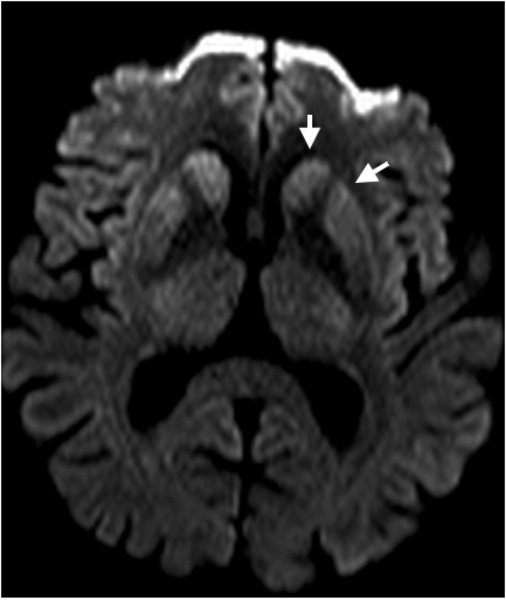

Creutzfeldt-Jakob - DWI Vergrößerung - axial

Typische kortikale Signalsteigerung in der Diffusionwichtung.